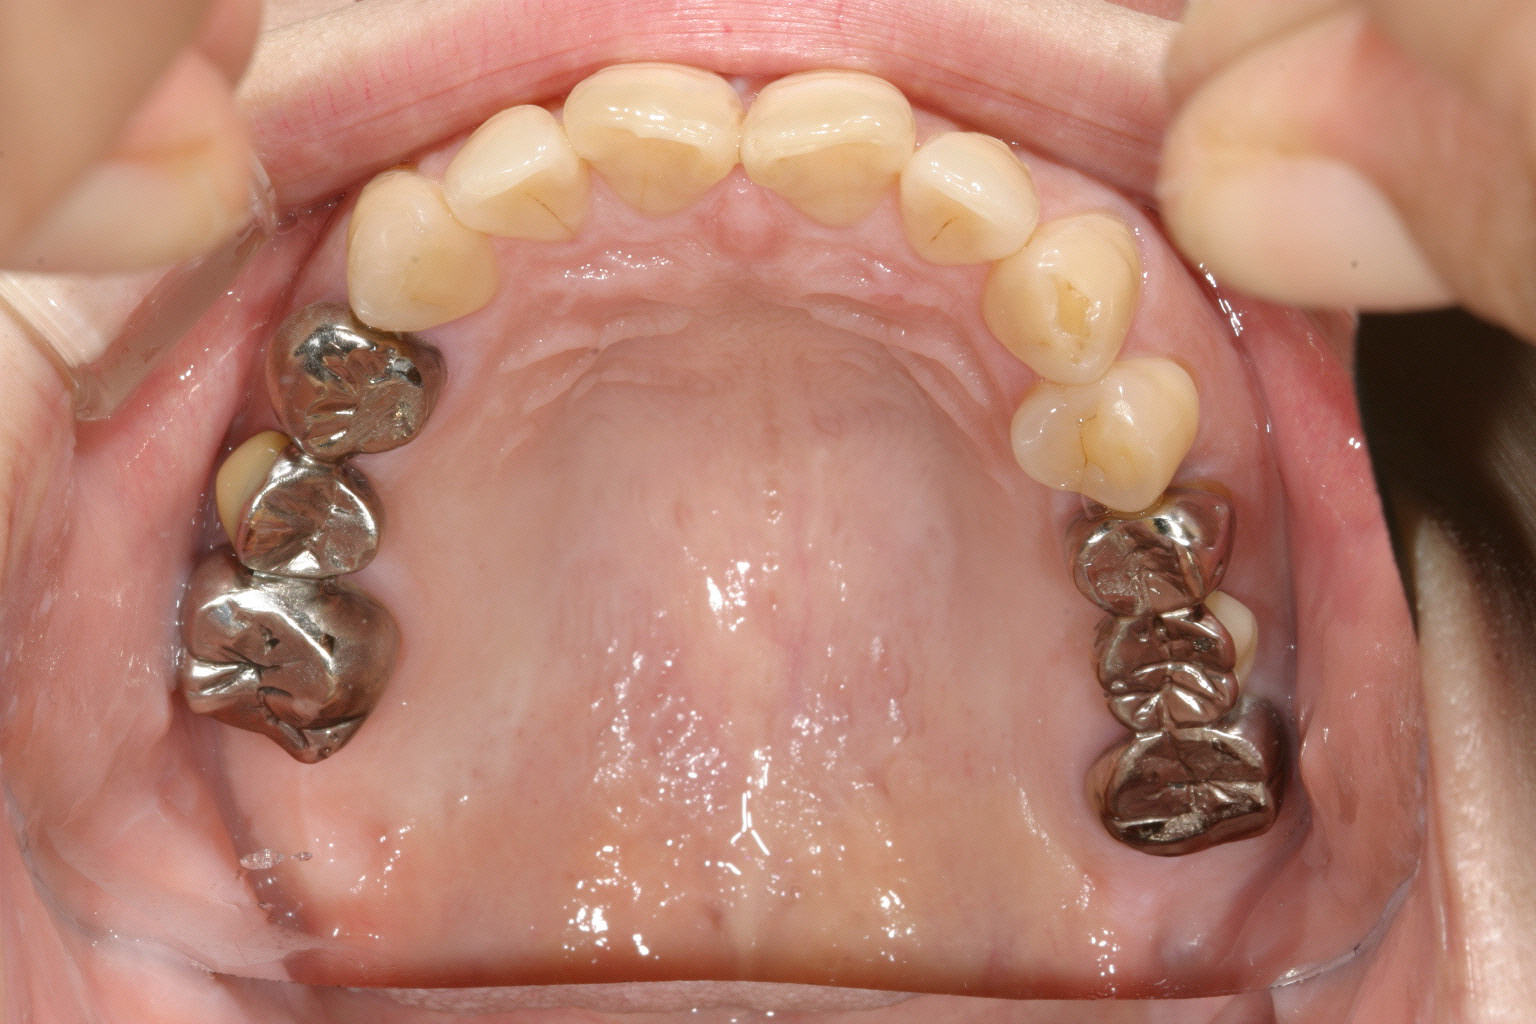

奥歯に金属のブリッジが両サイドに入ってますがかなり高さが低いです。

下の奥歯は歯抜け状態で上と上手く噛めてません。